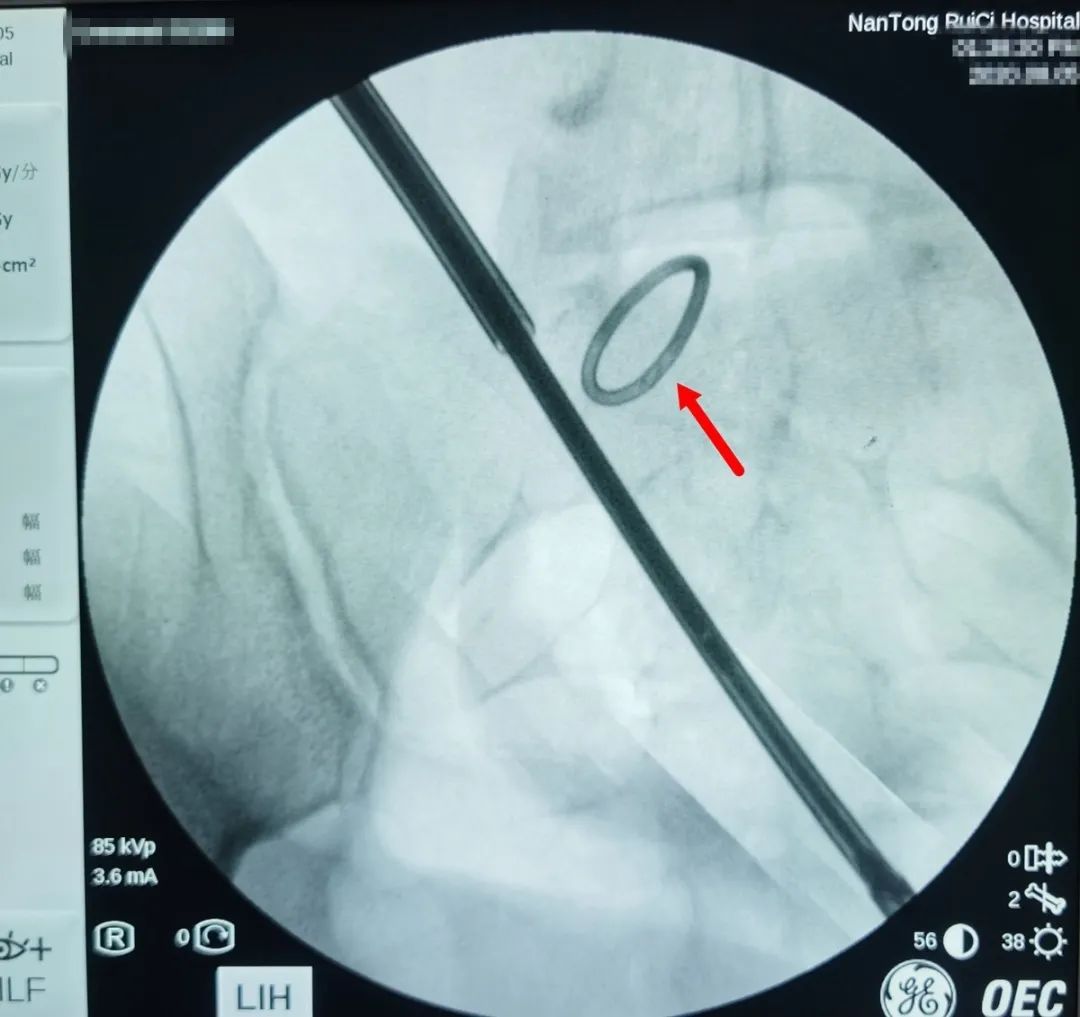

△術(shù)中X光,可清晰看到節(jié)育環(huán)。

通過反復(fù)的X光定位,醫(yī)生終于發(fā)現(xiàn)了節(jié)育環(huán)的蹤跡,這枚“O”型節(jié)育環(huán)已經(jīng)跑到了乙狀結(jié)腸中段右側(cè)系膜內(nèi),并且穿透了乙狀結(jié)腸右側(cè)壁肌層,貫穿腸腔。醫(yī)生分離切開腸系膜后,看見有近一半的節(jié)育環(huán)嵌頓在腸腔內(nèi)。